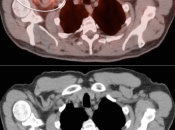

Extravasation of Injected FDG

FDG is injected intravenously. As many cancer patients have challenging venous access issues, partial extravasation of FDG during injection is not uncommon (an estimated 10% of patients have evidence of extravasation on their PET images).

Extravasation of FDG at the time of the intravenous injection can result in false positive interpretations due to:

- Focal intense uptake at the injection site.

- Linear uptake along the lymphatic channels within the arm (appearing as long vessels).

- Focal uptake in small ipsilateral axillary nodes.